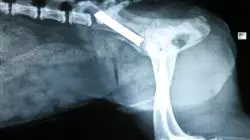

Thus, the intramedullary nail, for a long time, has been the most widely used implant in veterinary medicine because it is placed in the medullary cavity and becomes resistant to bending in all directions. Its strength is related to its diameter and its ability to restrict the movement of the fractured bone fragments. It is the most commonly used fastening system for dogs and cats.

The teaching team of this Fracture Fixation Methods Expert has made a careful selection of the different state-of-the-art techniques for experienced professionals working in the veterinary field. Specifically, this specialization focuses on the study of skeletal external fixators and circular fixators, intramedullary nailing, and bone plates and screws.

External fixation of fractures is the use of a rigid support placed outside the body and connected to the bone by means of needles through the skin (transcutaneous). The placement technique with respect to other methods of internal osteosynthesis shows that external fixation improves the biological environment preserves soft tissue and irrigation, accelerates healing, decreases the risk of infection and reduces surgical time.

The external fixator provides stable fixation of the bony ends without the need for implants in the fracture line or immobilization of neighboring joints, and is therefore particularly suitable for open, exposed or infected fractures. It allows to compress, neutralize or distract the bony ends depending on the need of the pathology.